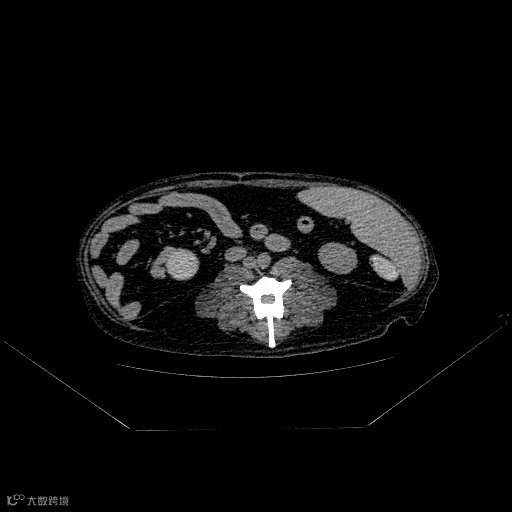

是确保诊断区域图像质量的关键因素。标准的摆位减少断层图像的变形,利于直接诊断,同时减少非诊断区域对诊断区域的干扰和导致的部分伪影。

双后肢未拉直

影响髋部观察